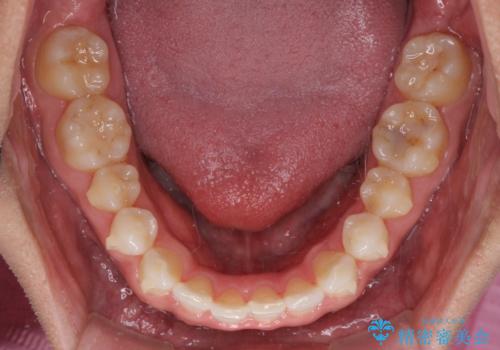

- 上下前歯のデコボコを気にして来院された患者様です。

以前矯正をした後戻りということで、歯列不正はそれほど大きくなかったため、インビザライン・ライトを用いて矯正治療を行うこととしました。

1日22時間以上しっかりと装着してくださったので、半年かからずに治療を終えることができました。